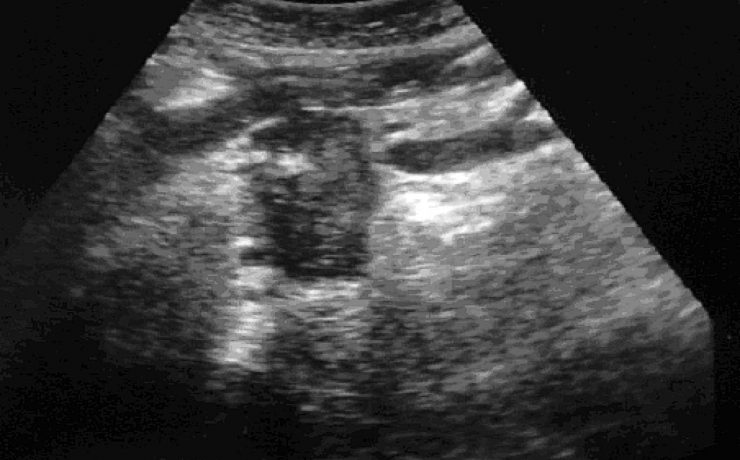

Caso clínico Se presenta un caso clínico de hematocervix diagnosticado por ultrasonografía en una paciente peri menopáusica sin antecedentes de patología cervical. Se discuten las causas de esta alteración, la utilidad del diagnóstico por ultrasonido, su tratamiento quirúrgico y su relación con patologías en otros órganos y sistemas. Introducción La